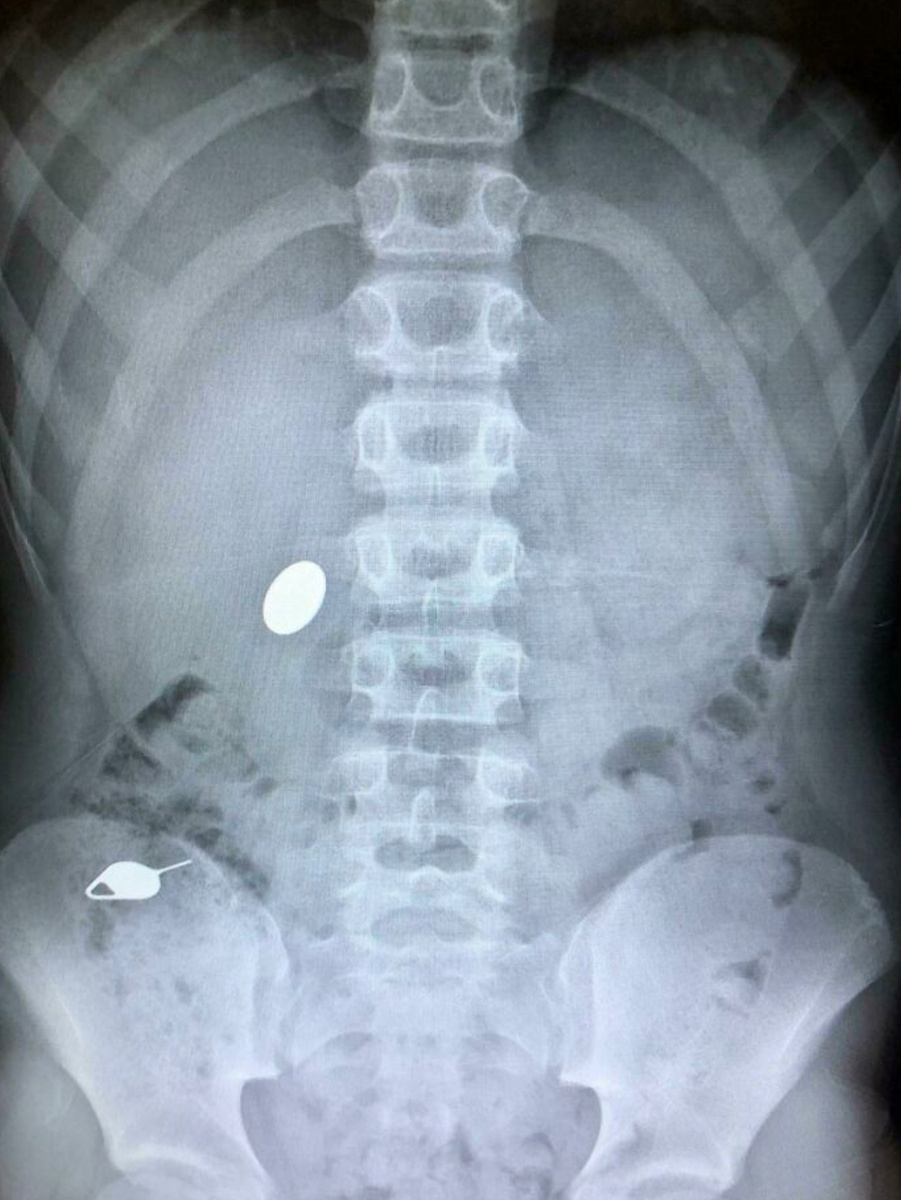

Сначала мой сын по чистой случайности проглотил ключик для SIM-карты. Но потом он уже осознанно проглотил монету, чтобы показать брату, как так вышло

«Все случилось пару лет назад. Сын игрался с ключиком для симки, и как-то так получилось, что он его проглотил. Потом он решил зачем-то показать своему брату, как так вышло с ключиком, и в качестве примера проглотил монетку. Как только я узнала об этом, мы сразу отправились в больницу, нам сделали снимок. Доктор сказал, чтобы посторонние предметы могут выйти естественным путем, поэтому я должна обращать внимание на стул сына. Если же не выйдет, то потребуется операция. К счастью, все обошлось, и ключ и монетка вышли естественным путем».